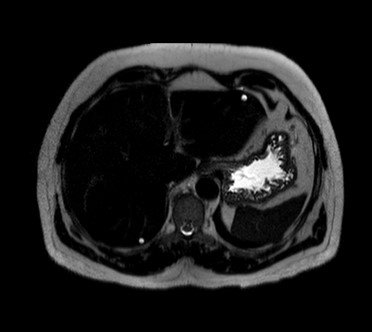

–MRI: markedly T2 hyperintense (light-bulb bright)

T2 :Hypo to slightly hyperintense

Central scar